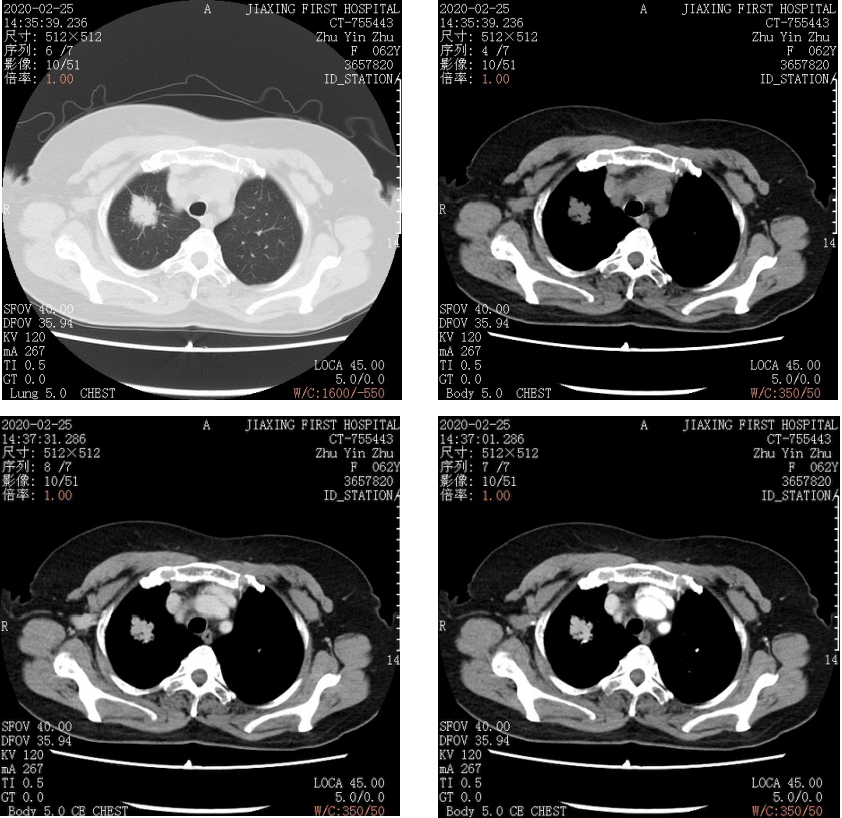

231.CT-755443:女,62岁。体检发现右肺上叶结节。